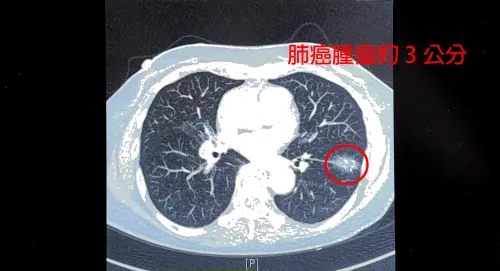

一位75歲女性患者,不菸不酒,今年安排健檢肺癌篩檢,發現左下肺葉有一顆接近3公分的惡性腫瘤,中國醫藥大學新竹附設醫院胸腔外科醫師謝義山表示,患者曾在10多年前罹患「肺結核」,後續得到肺癌的機會,大概是正常人的40倍到200倍,且台灣女性肺癌患者,80%至90%以上,皆不菸不酒。

▲一位75歲女性患者,被發現左下肺葉有一顆接近3公分的惡性腫瘤。(圖/中國醫藥大學新竹附設醫院提供) 肺癌早期症狀不明顯 及時就醫很重要